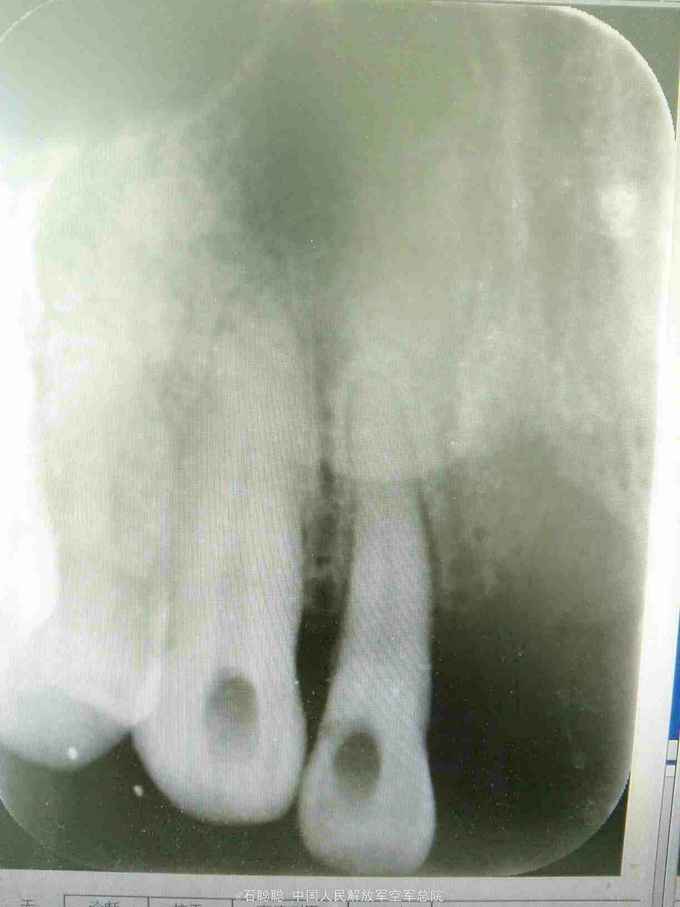

检查:11、21缺失,弹性义齿修复,牙槽脊欠丰满,12、22松动1度,13、23无松动,12、13、22、23未见明显龋坏 根尖片:12、22牙槽骨轻度水平吸收,13、23牙周膜及根尖未见明显异常

诊断:11、21缺失 治疗计划:向患者交代种植、活动、固定义齿修复方案的优缺点,患者考虑到种植周期长、活动修复难以满足美观要求,选择全瓷固定桥修复方案,但患者12、22基牙条件不甚理想,交代患者修复后要严密观察,定期复诊。 处置:12、13、22、23碧蓝局麻下开髓,拔髓,冲洗,置失活剂,氧化锌暂封 一周后复诊:去除暂封,测量根长,12=22=19mm,扩大至25#,13=23=24mm,扩大至35#,大量冲洗,干燥根管,置CP棉球,氧化锌暂封。 一周复诊:12、13、22、23去除暂封,试主尖,冲洗,干燥,冷测压充填,拍摄根尖片,恰填,置干棉球,氧化锌暂封 一周后复诊:12、13、22、23无不适,去除暂封,磷酸锌垫底,树脂充填,预备牙体,排龈,聚醚取模制作临时冠,调磨粘固 一周后复诊:试戴内冠,就位顺利,边缘密合 一周复诊:试戴全瓷桥,由于边缘密合,固位良好,调节正中咬合、前伸咬合、侧方咬合为轻接触,磨光U200粘固